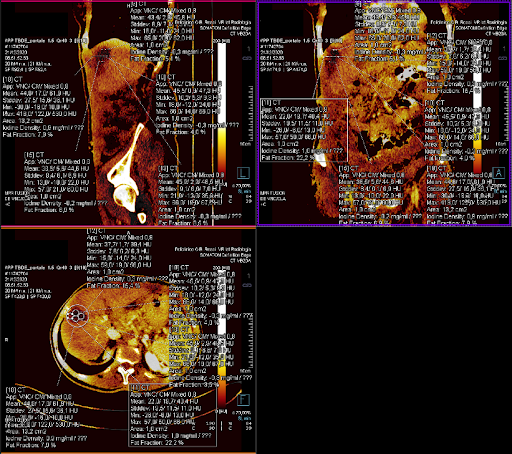

image

FIGURA 1. Esempio di alcune scansioni TC sul medesimo piano del protocollo adoperato per lo studio: pre-contrastografiche (A), in fase arteriosa (B), venosa (C) e tardiva (D). È inoltre possibile osservare ll'ipodensità al passaggio epatico S8-in esiti di trattamento post-ablativo.

FIGURA 2. Analisi VNC sul piano assiale. Sono ben visibili le 4 ROI centrali e la ROI centrale con incluso un bordo di 5mm nel parenchima epatico circostante.

FIGURA 3. Analisi VNC in proiezione sagittale, in cui si evince la distanza cranio-caudale tra le ROI superiore, centrali e inferiore.

FIGURA 4. Esempio di analisi VNC in tre diverse proiezioni: sagittale (in alto a sinistra), coronale (in alto a destra) e assiale (in basso). Ben visibili i le informazioni estratte da tutte le ROI tracciate.

FIGURA 5. Esempio di analisi VNC con mappa dello iodio. Sono visibili le ROI di 1 cm2 tracciate manualmente sul piano assiale con i rispettivi valori ottenuti. Rispettivamente: la ROI superiore (A), tre ROI sul piano centrale (B-C-D), la ROI inferiore (E) e la ROI centrale con incluso un bordo di parenchima di 5mm (F).